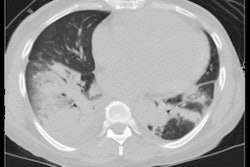

CT scans were performed on these patients at a median of three days from the onset of symptoms. After generating 360-degree VR scans from each CT exam using VR visualization software (Surgical Theater), the researchers then performed volumetric analysis to calculate lung volume data.

The percentage of diseased tissue was determined by comparing the disease volume with the overall lung volume, normalized for body surface area. The authors were blinded to both clinical and laboratory data during image segmentation.

Although there wasn't a significant correlation between the extent of lung infection and outcomes, there was a statistically significant difference in the volume of infected lung tissue between those who survived and those who didn't. This significant difference was also evident when the infected lung volume was normalized to the patient's body surface area.

| Infected lung volume (cm3) | 346.32/257.58 | 597.72/628.55 |

| Infected lung volume/body surface area (cm3/m2) | 172.26/106.85 | 304.32/379.67 |